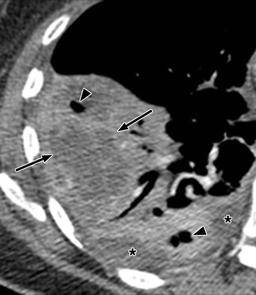

【影像表现】:ct平扫横断面肺窗示左侧脏层胸膜线和气液平面(↑).

左侧胸腔巨大的气液平面